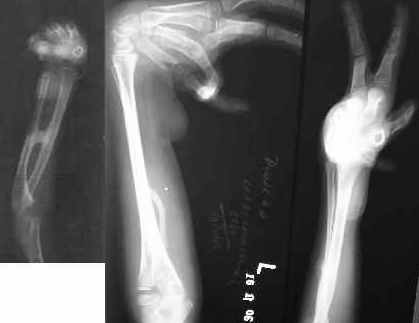

Etiology: Post burns contractures of the hands and the wrists Time elapsed since episode: 9 months In frame time: 7 weeks follow up after 4 years (his son had a compound supracondylar femoral fracture and he brought him to us for treatment from approximately 1600 kms away!)

Distraction is ideally suited for such instances. The UMEX fixator is perfect. Light and yet strong. Erected on smooth pins and with differential distraction and gradual angular (manual) correction, the wrist and the finger deformities will most certainly correct to a great extent. ((A computer modified model picture of the frame is attached)

The synostotic bridge must be excised (along with preventive measures to try and prevent a recurrence) at the time of the application of the frame.